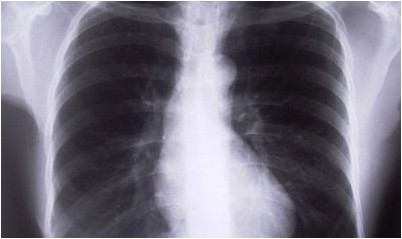

К сожалению, кожная проба не на 100% точна и, как было известно, дала неправильные положительные и отрицательные чтения.Однако существуют другие анализы, которые доступны, чтобы диагностировать TB. Анализы крови, рентген грудной клетки и анализы мокроты могут все использоваться, чтобы проверить на наличие бактерий TB и могут использоваться вместе с кожной пробой.Лекарственно-резистентный туберкулез более трудно диагностировать, чем регулярный TB.